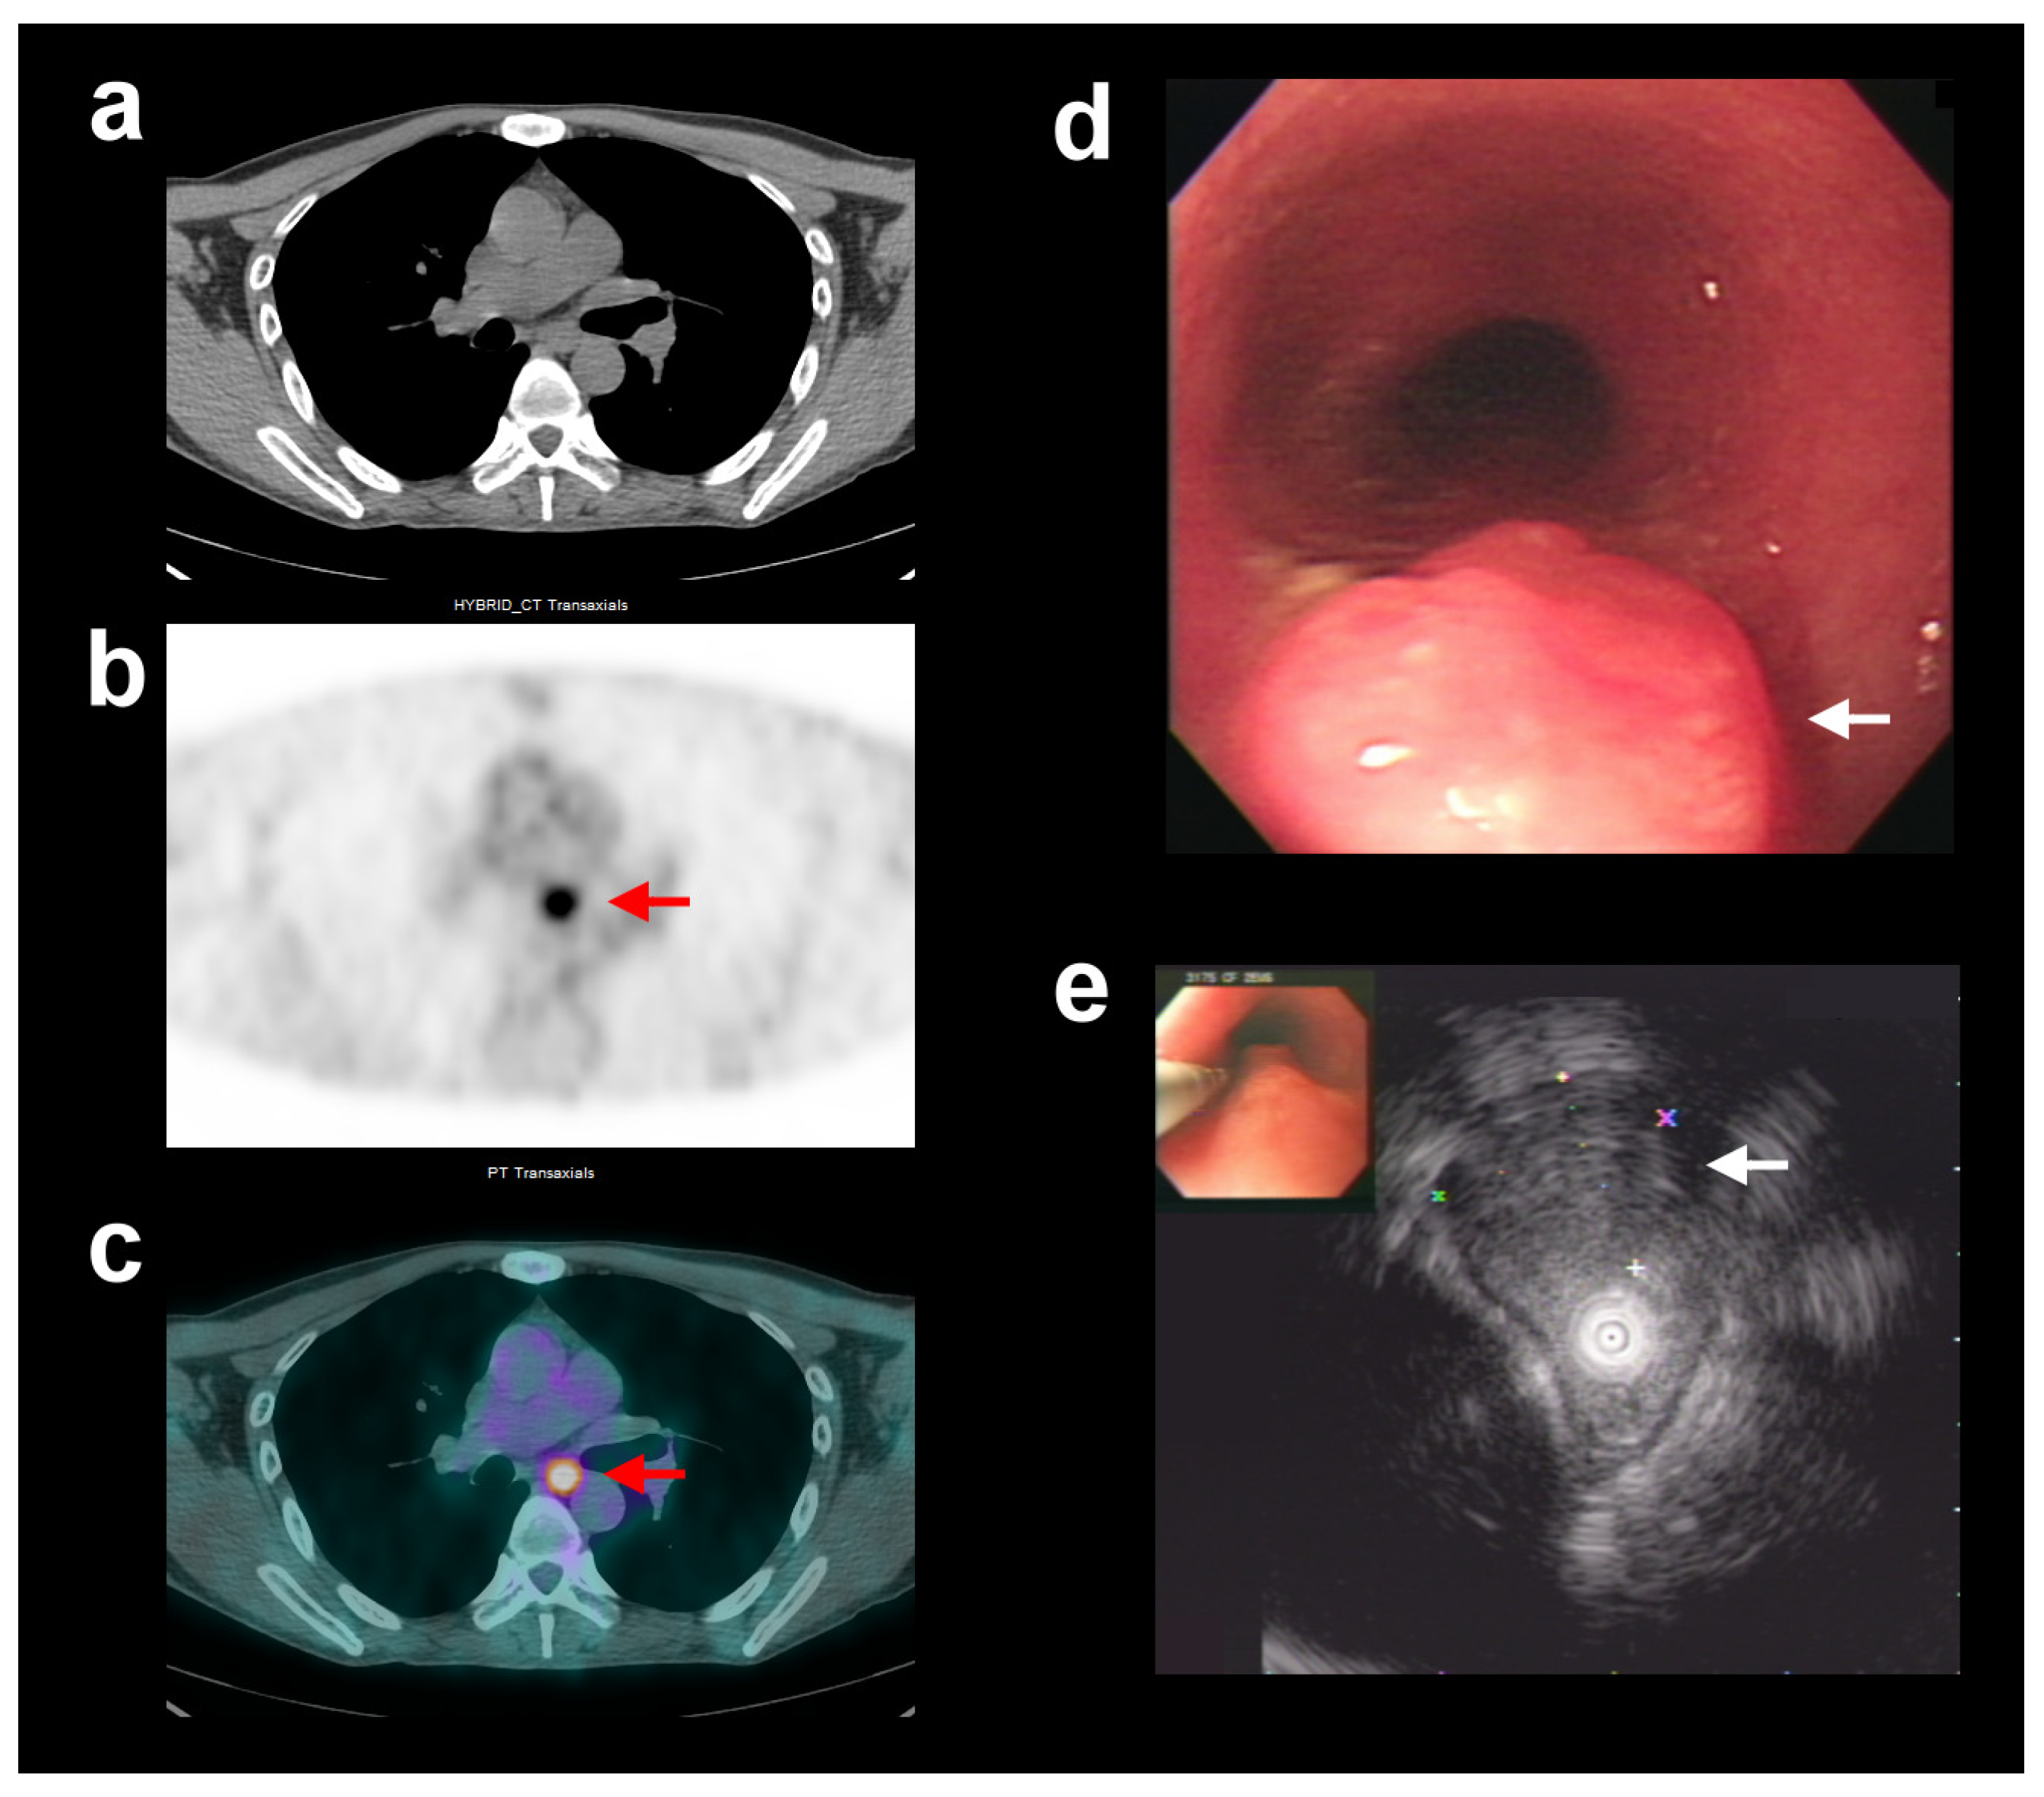

Figure 1. In the group of patients with esophageal squamous cell carcinoma who did not receive neoadjuvant chemoradiotherapy (CRT[−]sub group), a 47-year-old man showed unexpectedly high FDG avidity in the polypoid esophageal tumor. Representative transaxial computed tomography (CT) (a), positron emission tomography (PET) (b), and fused PET/CT (c) images showed a focal area of increased FDG uptake in the middle thoracic esophagus (red arrows, SUVmax = 5.8, fT2). Endoscopic ultrasound (EUS) (d,e) showed a polypoid tumor at about the 27 cm level from central incisors with the invasion of the muscularis propria (white arrows). The application of corrected SUVmax for exophytic-type tumor, by coordinating FDG PET/CT and EUS, revised the complementary T-stage classification from T2 to T1, which was consistent with the final pT1 stage determined via post-surgical histopathology.